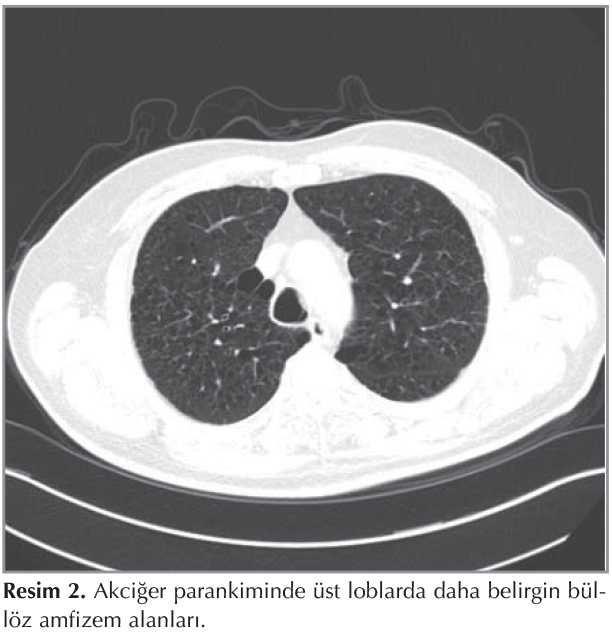

Olgumuz efor dispnesi nedeni ile polikliniğe başvuran altmış ?? yaşında erkekti. Fizik muayenesinde sağ ?st zonda nadir alanlar da ronk?sler duyuldu. ?zge?mişinde 40 paket/yıl sigara ?yk?s? mevcut olup 8 yıldır sigara kullanmıyordu. PA akciğer grafisinde diyafram konturları d?zensiz, amfizemat?z havalanma artışı ve bilateral pulmoner arterleri geniş izlendi (Resim 1). Solunum fonksiyon testinde FEV1: 3.28L (%120), FVC: 4.26 L (%123) ve FEV1/FVC: %77 idi. Karmonmonoksit dif?zyon testi %43 mmol/kPa/min idi. Ekokardiyografi incelmesinde ejeksiyon fraksiyonu %60 ve sistolik pulmoner arter basıncı (PAB) normaldi. Toraks BT'de akciğer parankiminde havalanma artışı ve ?st loblarda daha belirgin yaygın b?ll?z amfizem alanları ve her iki akciğerde interlobular septalarda hafif kalınlaşmalar ve milimetrik interstisyel nod?ller mevcuttu (Resim 2,3).

Resim 2